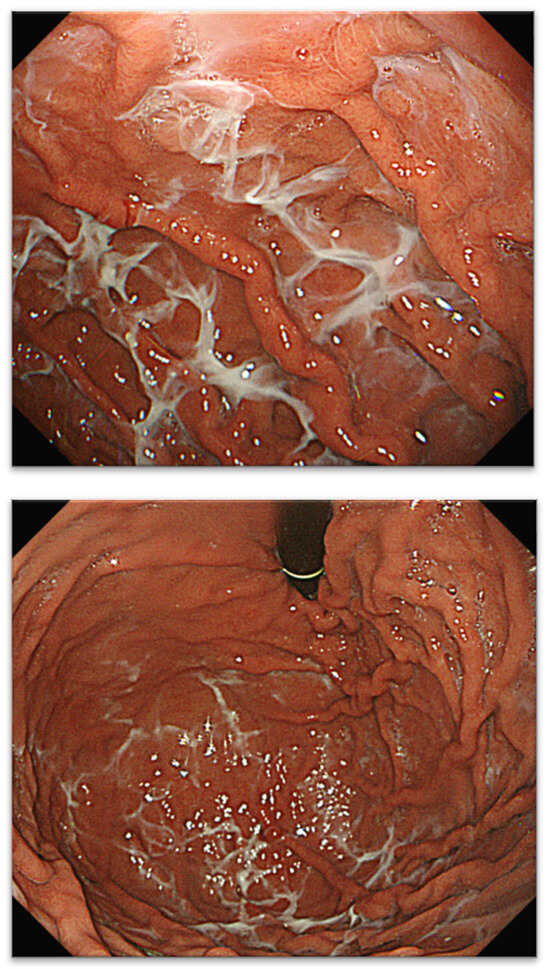

2.1. Definitions of Web-like Mucus